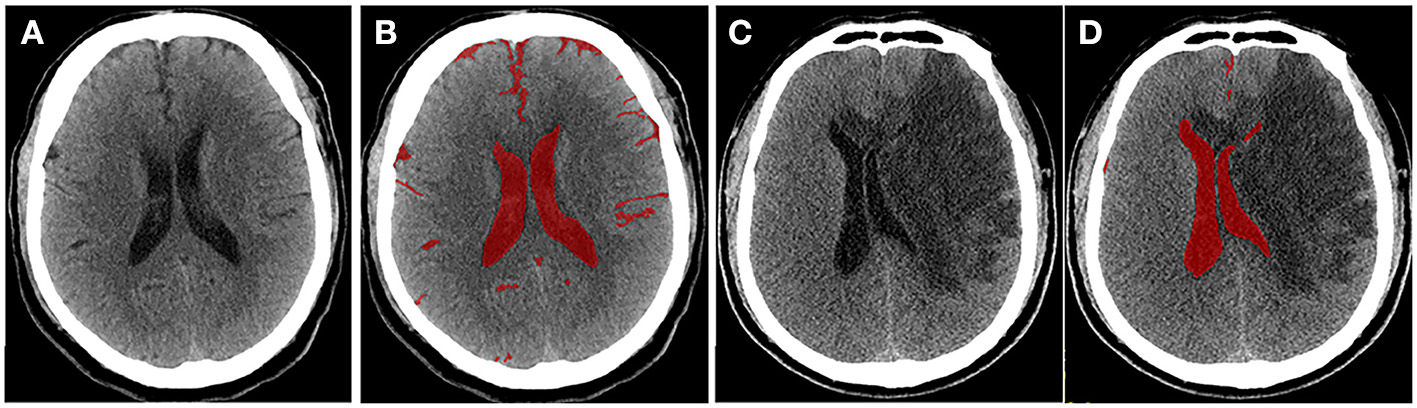

To quantify the severity of edema more accurately, Dhar et al. proposed a CT-based volumetric measure of CSF shifts over time (19). As ionic and vasogenic edemas develop, the CSF is progressively displaced from the sulci and ventricles of the cerebral hemispheres to compensate for the increased brain tissue volume in the fixed cranial cavity. Supratentorial CSF spaces (sulci and ventricles ipsilateral and contralateral to the stroke and the third ventricle) and basal cisterns are outlined on each slice, and the volume of CSF is quantified (Figure 2). The CSF can be pushed out of the hemispheric sulci, cerebral ventricles, and basal cisterns as edema develops in the hours or days following the stroke. Studies have shown that, compared with MLS, the reduction in CSV (ΔCSF) from baseline to follow-up CT is an earlier and more sensitive indicator of edema severity across a broader dynamic range (46, 47). Furthermore, the authors developed an automated algorithm to segment the CSF from the CT scans of stroke patients (46) to facilitate and scale up such approaches. However, their method measures changes in the brain volume (BV); thus, it cannot distinguish edema from infarct growth or hemorrhagic transformation. Moreover, it is not suitable for patients with stroke in the brainstem or cerebellum.

Figure 2

Quantitative cerebrospinal fluid (CSF) shifts. Baseline (A) and 24 h (C) follow-up CTs after ischemic stroke, respectively. CSF spaces are outlined on a CT scan slice at baseline (B) and follow-up (D). Supratentorial CSF and basal cisterns were outlined on each slice, and ΔCSF was subsequently calculated.